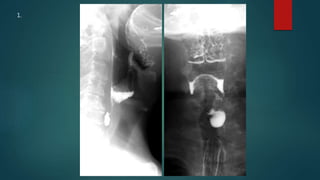

This document appears to be a medical report discussing several patients. It mentions a 35-year-old who was in a severe motor vehicle accident and an 81-year-old with a history of a non-vegetarian diet who had a perforated bowel from a chicken bone. The document provides few other details across its 25 numbered entries and was authored by Dr. Anish Choudhary for junior year 3 on May 30, 2016.